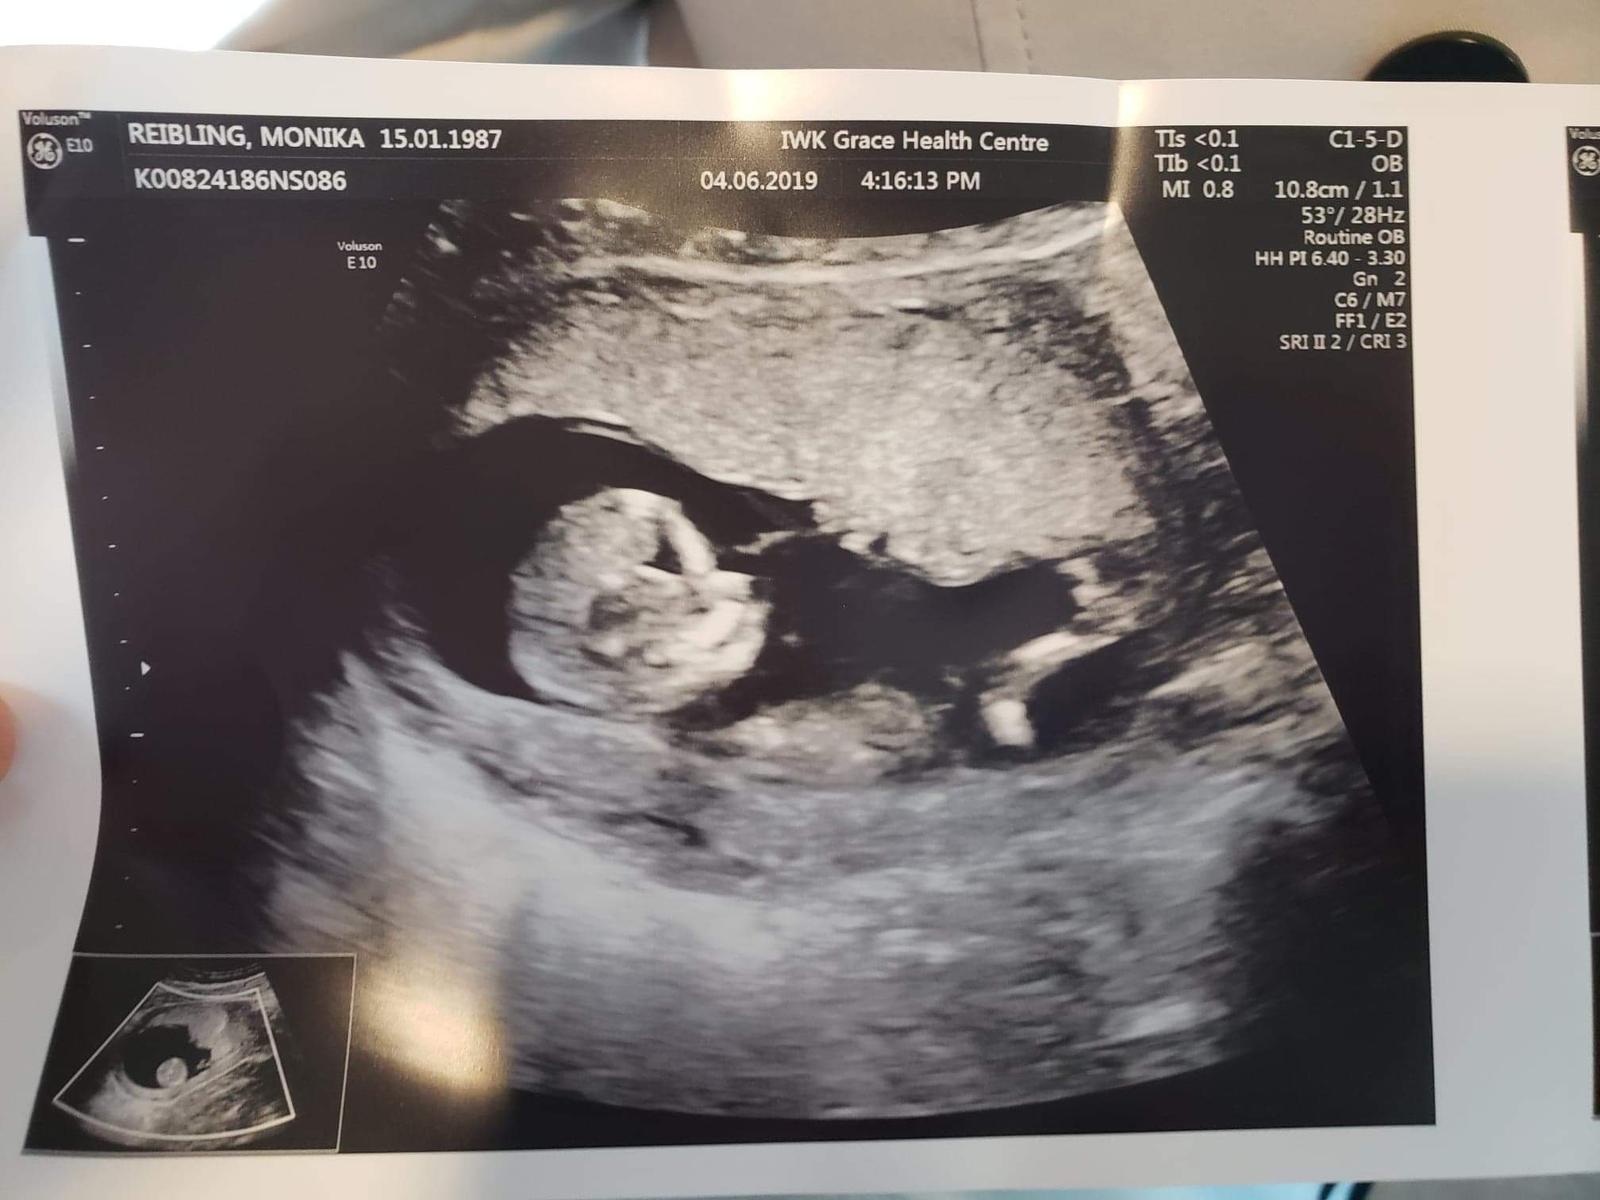

Ahojte, tak dnes na kontrole všetko v poriadku🙏💞🍀maličké sa hýbali, bolo to nádherné😊 13.6 idem na odbery a 17.6 mam kontrolu mam doniesť moc a ultrazvuk mi budu robiť a mala by som už dostať aj knižku. Termin pôrodu mam 24.12 teraz som 10+6tt